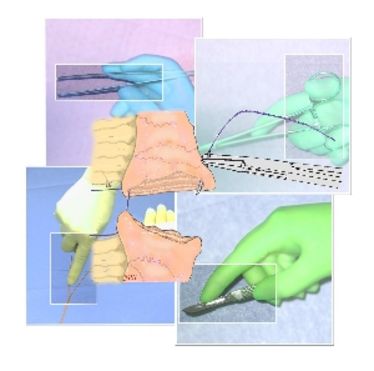

Hands-on-Kurs - Multiorganentnahme

Hands-on-Kurs - Multiorganentnahme

OP-Kurs "Mikrochirurgie der peripheren Nerven und Gefäße"

OP-Kurs "Mikrochirurgie der peripheren Nerven und Gefäße"